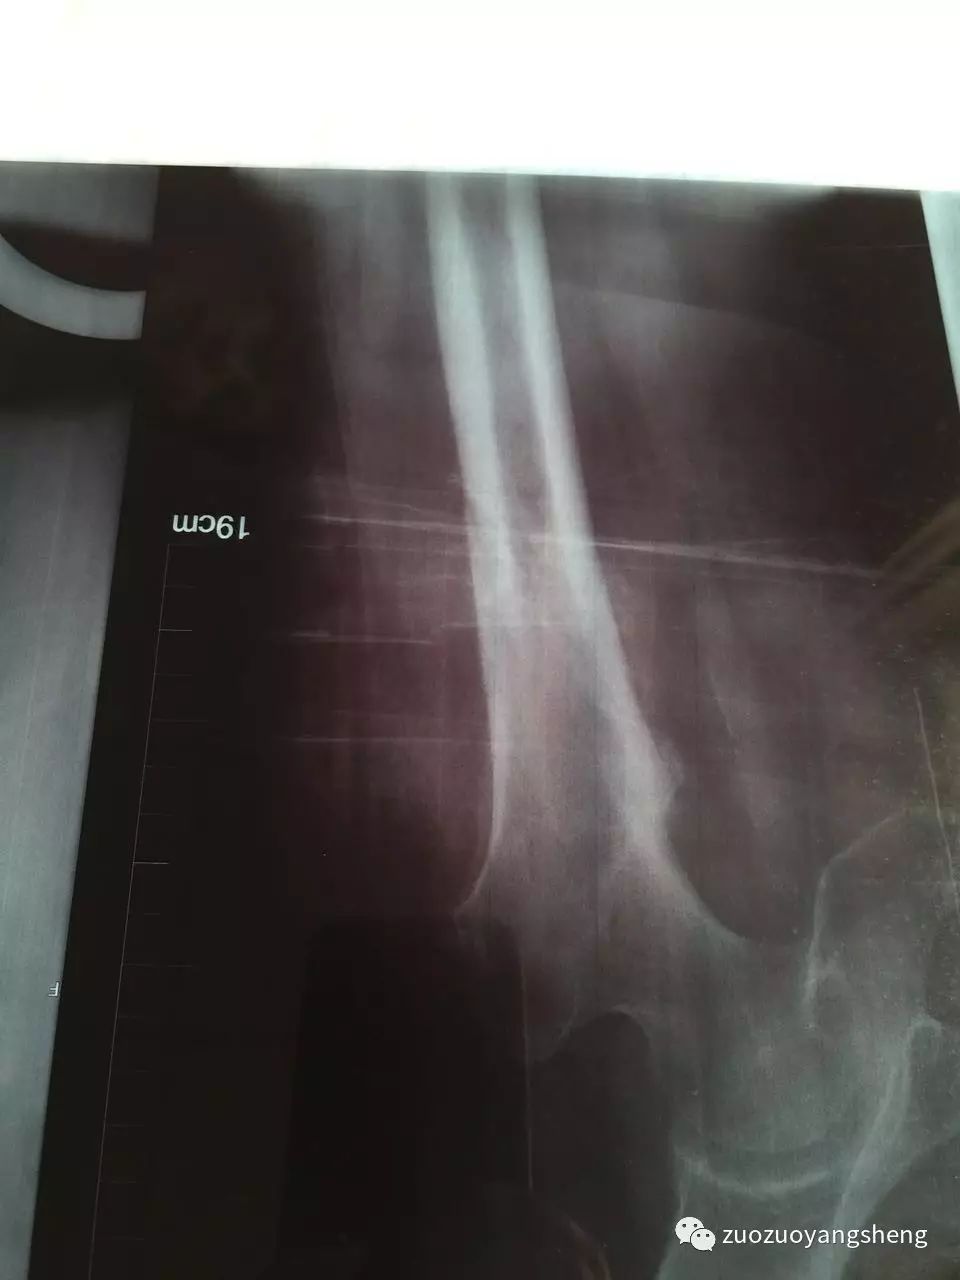

大家好,我是左左。在我收到方老师发过来的案例时,比较震惊,80几岁的婆婆能在短短几周里迅速愈合,确实有点不可思议。婆婆在某三甲医院的时候,医生是建议手术,而且必须手术。当家人选择保守治疗,选择使用原始点,才发现保守治疗的效果比手术治疗的效果更好,伤害更少,费用更低。

收到案例后的当天晚上,我就在想,自己母亲的粉碎性骨折是否也可以手法复位,保守治疗呢?然后开始陷入深深的自责中。去年母亲髌骨粉碎性骨折后,医院强烈建议手术治疗,说保守治疗可能需要在床上躺6个月,而且不能随意挪动。所以自己当时考虑到母亲不能动,长时间不能动,不能下床,更不能运动,这样下去怕影响整个身体,后决定采用医生建议,进行手术治疗。现一路走来,手术治疗这个方案,不到万不得已,原始点家人们尽量不要使用。手术前需要打针消炎(寒凉药物),手术中需要切割皮肤、肌肉等各身体组织,需要打麻药(超级寒凉药物),需要打钢钉固定骨头,手术后同样需要7天输液消炎(寒凉药物)……半年后还需要手术取出钢钉,还需要消炎(还好当时医院床位紧张,所以没有消炎,让回家自行打针消炎,我强烈反对,所以没打。)经过这样伤害性的治疗方法,虽然有给母亲使用原始点,按推、温敷和喝姜汤,但母亲的脚还是没能完全恢复。骨折至今已经8个月了,走路依然是一瘸一拐,膝关节里面还经常感觉紧绷,经常感觉疼痛。

如今,跟方老师提供的案例进行对比,骨折后选择手术治疗方案真的不是最佳治疗方案,遇到类似情况,特别是年轻人、小朋友,如果在遇到骨折后,选择保守治疗方案,配合使用原始点,因为身体热能足,也许修复起来更快更好。